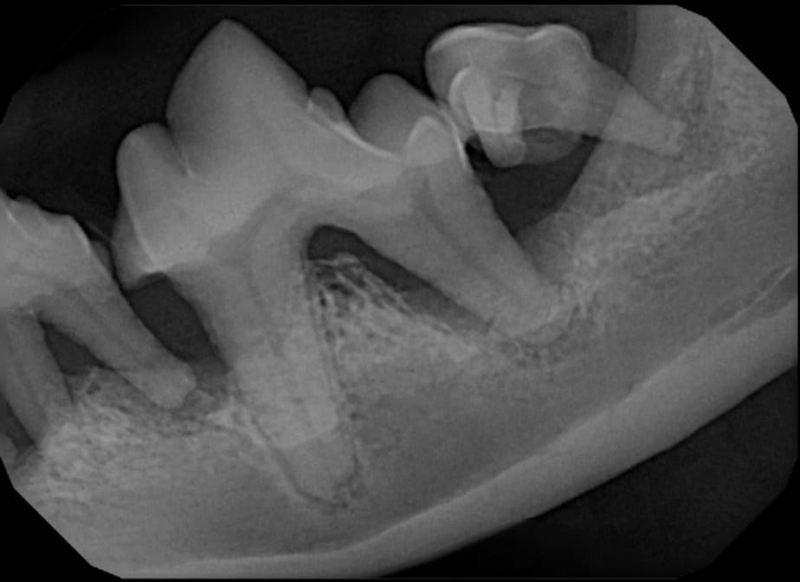

Tooth resorption is a disease process where the body begins to break down the adult tooth. It is widely known to occur in cats but can also occur in dogs. In cats these lesions are thought to be inflammatory, while in dogs they can be more of a replacement resorption process. These lesions can be very painful and should be treated, generally with extraction depending on the type of resorption that is occurring. The disease can be progressive and affect many teeth over several years. It is important to have regular checkups and yearly dental cleanings to monitor for these lesions.